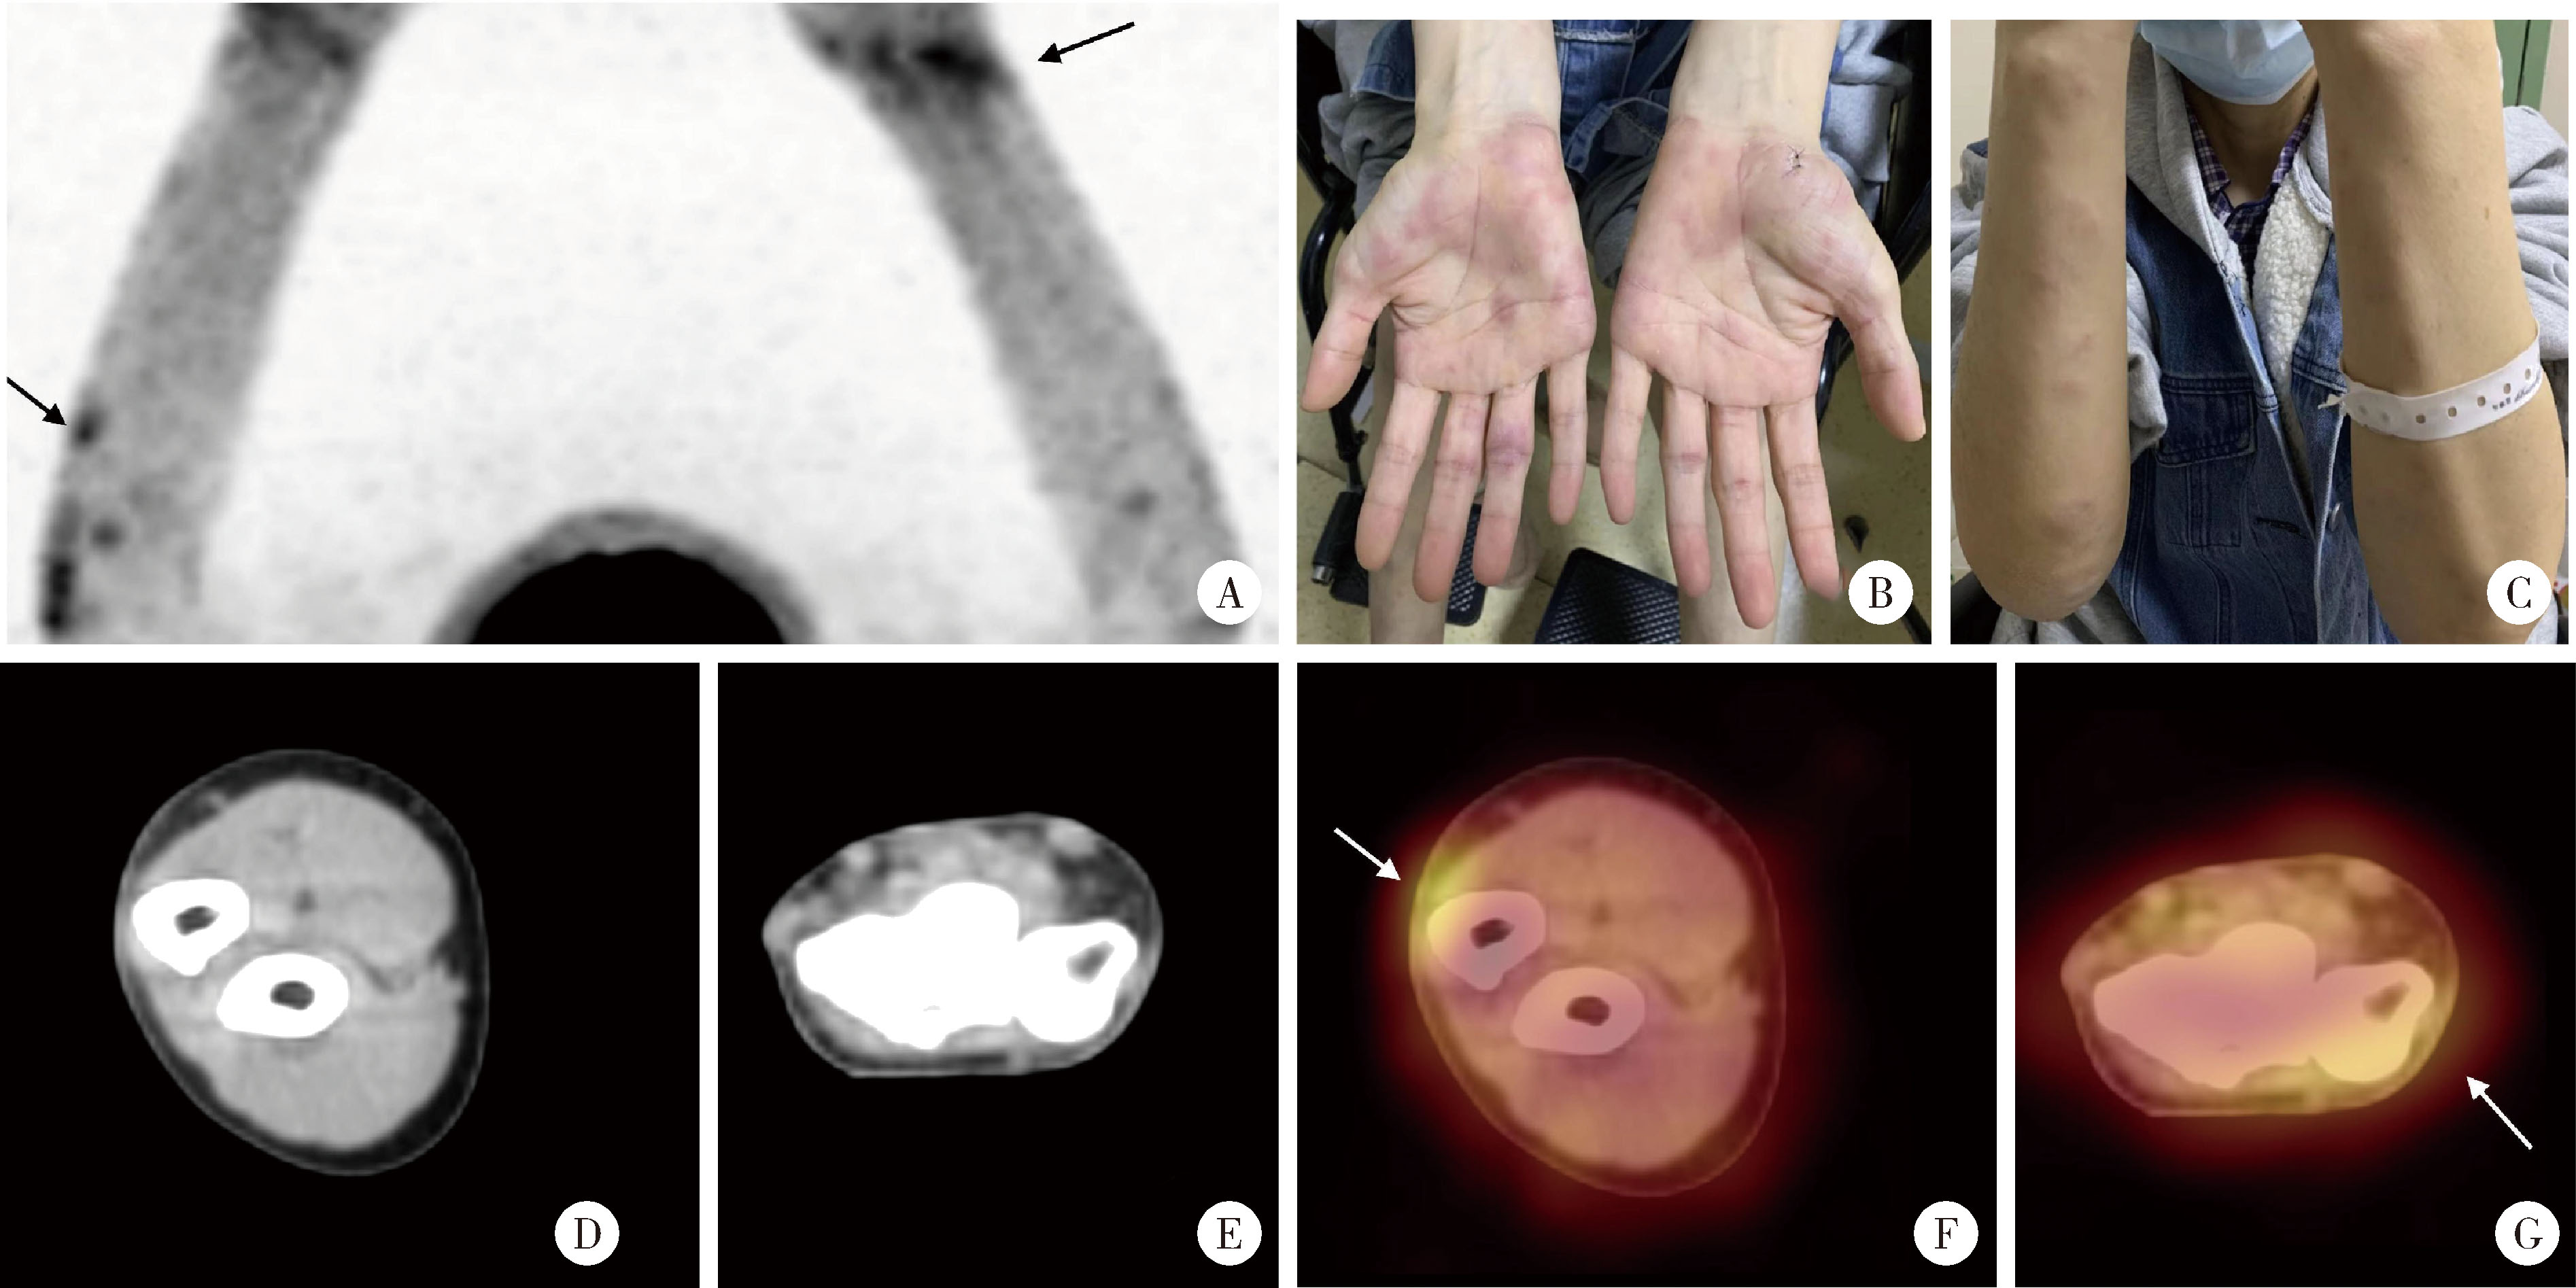

经典型Sweet综合征 18F-FDG PET/CT多脏器异常显像1例

Classical Sweet syndrome with multiple organ lesions by 18F-FDG PET/CT: A case report